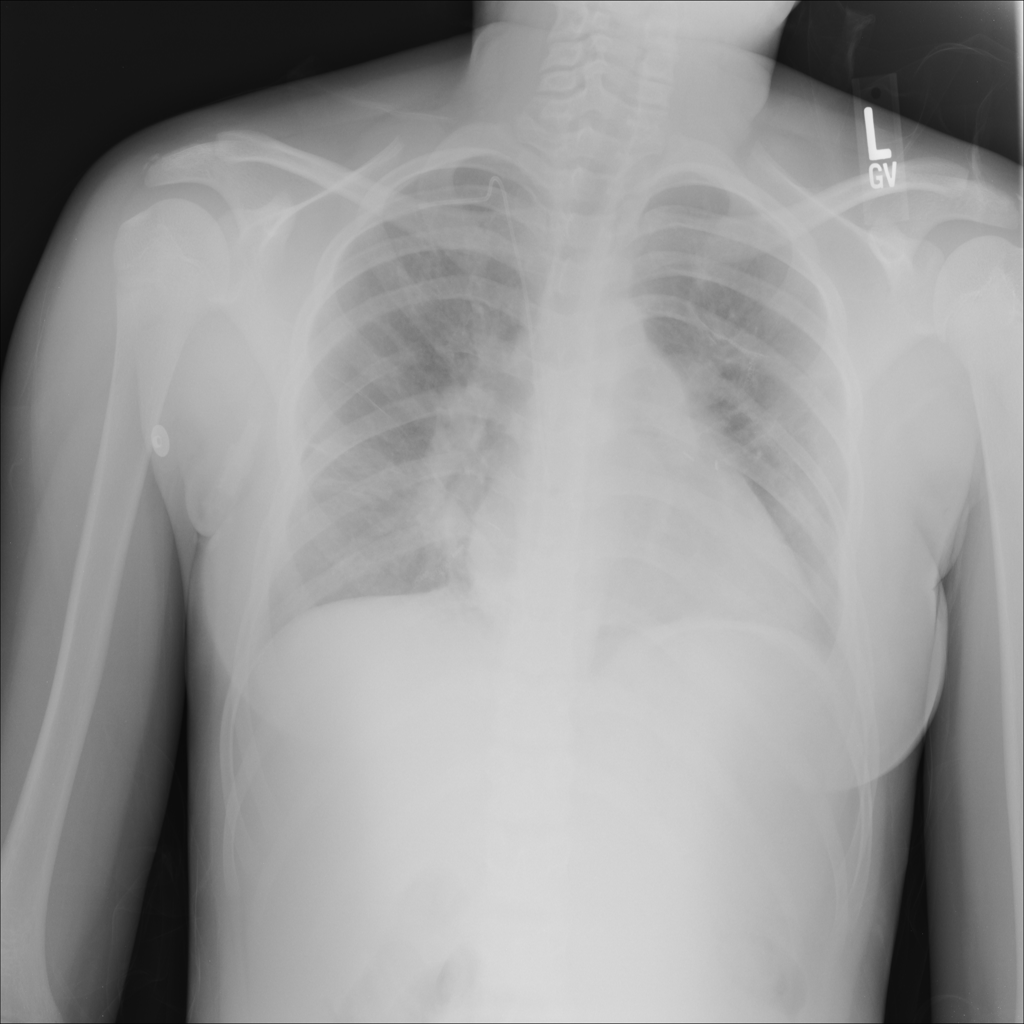

Consolidation

Consolidation refers to air-space filling that makes part of the lung appear denser on imaging.

Showing up to 90 reference images for Consolidation.

PAT-531A · IMG-006Consolidation

PAT-531A · IMG-006

PA